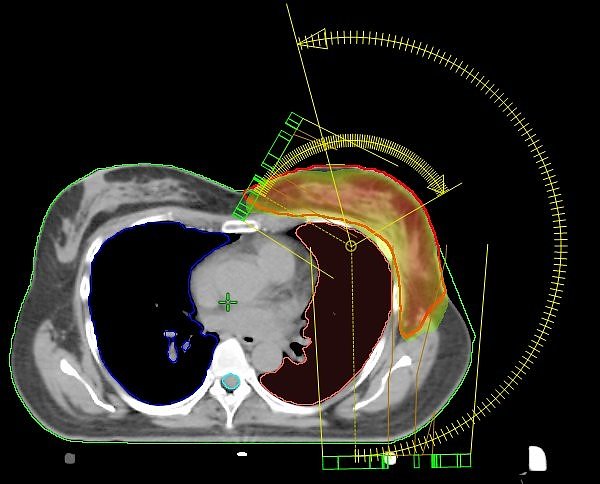

Einzigartig in Nordhausen: VMAT-Bewegungsbestrahlungstechnik mit 2 Bögen (Nordhäuser Standardtechnik); der Hochdosisbereich erfasst ausschließlich das Zielvolumen und die umgebenden Risikoorgane werden geschont.

Wir bestrahlen die Brust nicht standardisiert, sondern programmieren die Technik so, dass der Dosisverlauf individuell an die jeweilige Brust angepasst wird. Und das ist von Frau zu Frau immer unterschiedlich. Kollateralschäden an benachbarten Organen werden so auf ein Minimum reduziert”, berichtet der leitende Medizinphysiker Dirk Strauß.

Die seit dem Jahr 2009 im Südharz Klinikum eingesetzte Bestrahlungstechnik an den Linearbeschleunigern macht es möglich, den Bereich der Bestrahlung nicht nur geradlinig, sondern auch bogenförmig maßgeschneidert zu erfassen.

Was im Jahr 2009 mit den damals modernen Linearbeschleunigern in Nordhausen eingeführt wurde, das wird mit der Inbetriebnahme der neuesten Generation Ende vorigen und Anfang dieses Jahres konsequent fortgesetzt. Mit der jetzt vorhandenen Technik kann zudem die Bestrahlungszeit für die Tumor-Patienten auf rund 1,5 Minuten reduziert werden. Einmalig in der deutschen Krankenhauslandschaft, berichtet Dr. med. Wolfgang Oehler.